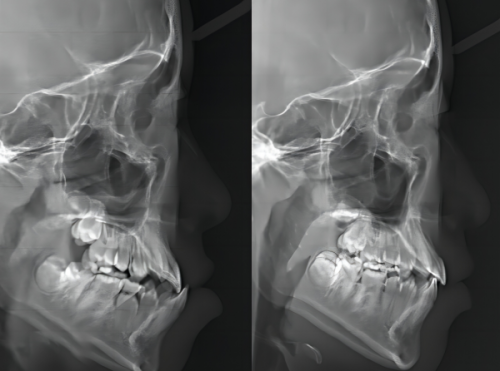

門診部花費大量資金引進了許多國內外精良的口腔診療設備,如智能化口腔掃描儀、全景X光機、雷射治療儀等。有了這些設備,醫生在看牙時能更準確、更效率高地發現牙齒隱藏的問題,治療也更有針對性。例如,智能化口腔掃描儀能快速掃描出牙齒的情況,讓醫生一目了然。

- 數字化種植:依托CBCT數據及口掃技術,進行術前模擬規劃,可能應用數字化導板,旨在提升種植位置的準確度,縮短手術時間。